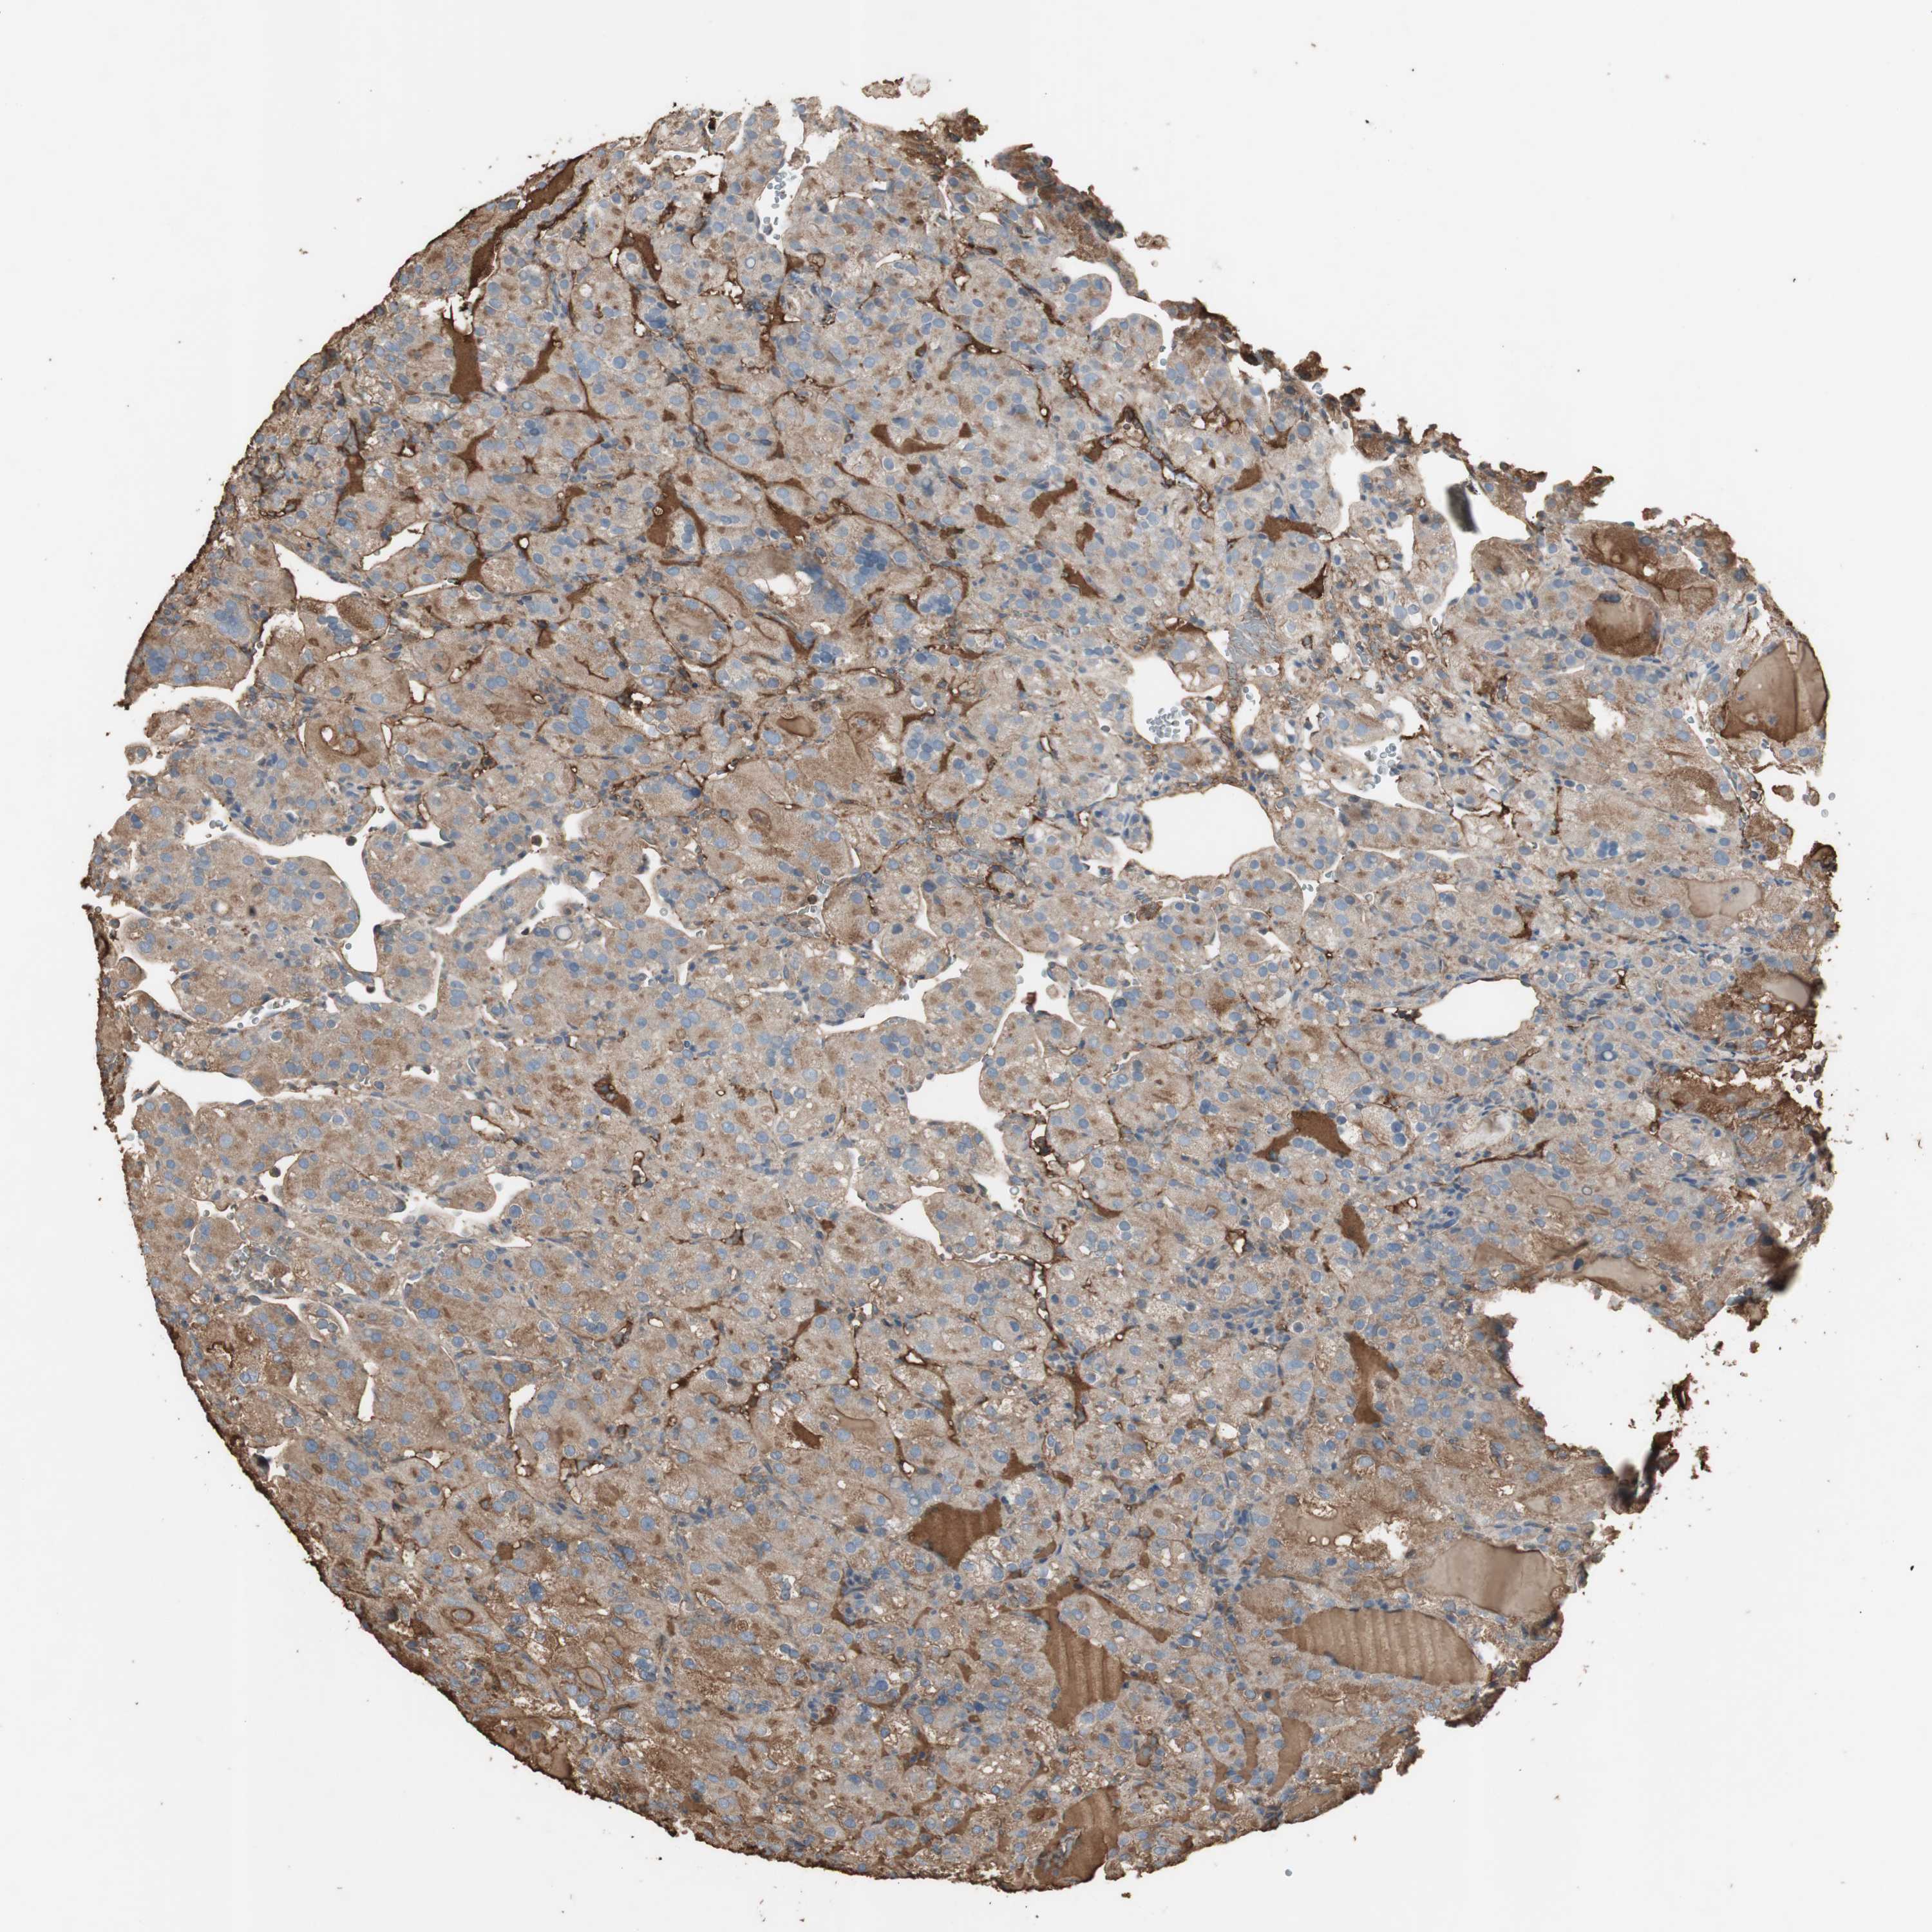

CANCER RENAL CANCER Show tissue menu

KICH TCGA KIRC TCGA KIRC VALIDATION KIRP TCGA PROTEIN RCC CPTAC PROTEIN EXPRESSION

Renal cancer

Kidney chromophobe